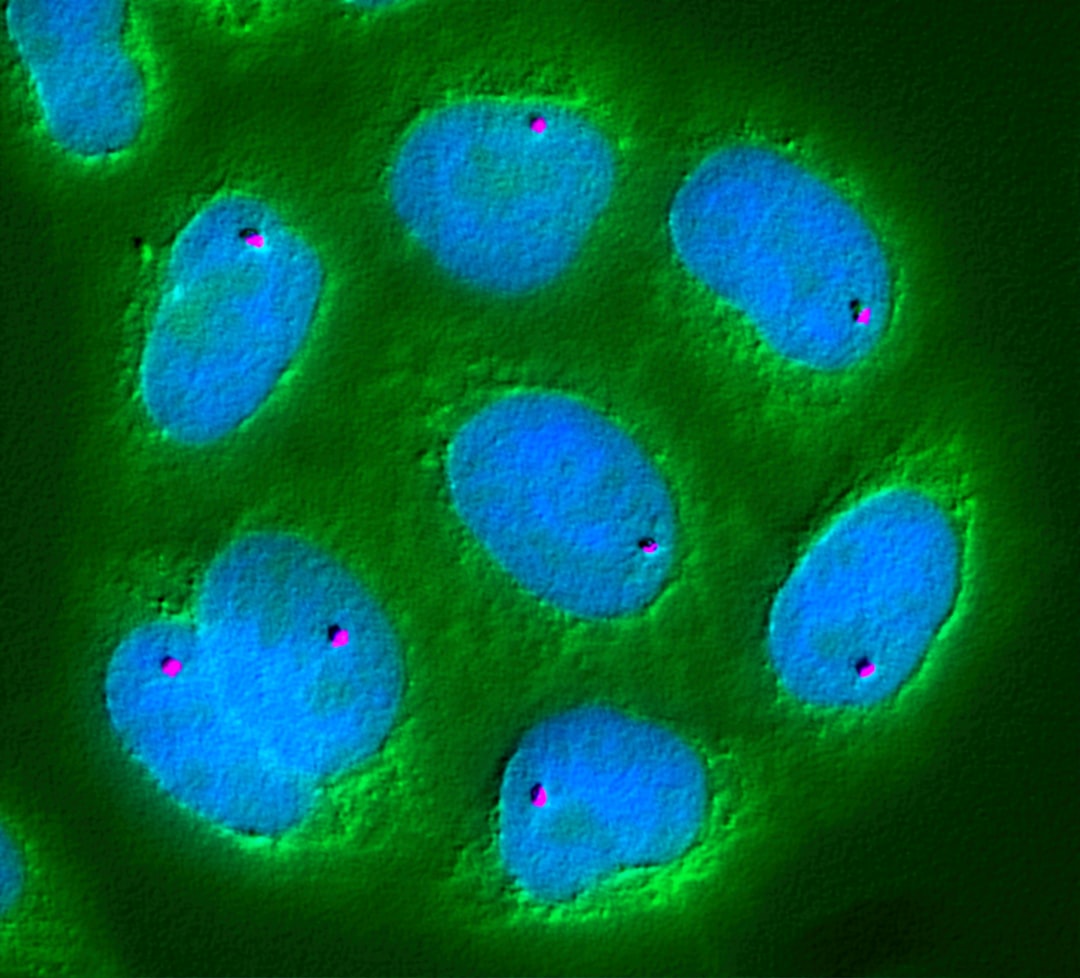

3. Imunoterapia Oncológica Personalizada: O Sistema Imunológico como Seu Aliado Estratégico Contra o Câncer

Imagine o seu sistema imunológico, não como um mero defensor, mas como um exército altamente treinado e personalizado para atacar precisamente as células cancerígenas. Em 2026, a imunoterapia oncológica personalizada deixará de ser promessa para se tornar realidade, redefinindo os protocolos de tratamento e abrindo um horizonte de esperança com eficácia e segurança sem precedentes.

A evolução das terapias com células CAR-T (Chimeric Antigen Receptor T-cell) será um divisor de águas. Imagine células projetadas sob medida, com engenharia genética precisa para identificar e aniquilar células cancerosas específicas. Essa nova geração de terapias CAR-T superará a resistência tumoral e a toxicidade, expandindo o tratamento para uma variedade ainda maior de tipos de câncer, inclusive tumores sólidos antes intratáveis.

A sinergia entre imunoterapia e outras modalidades de tratamento, como radioterapia e quimioterapia, será meticulosamente otimizada. Evidências recentes já demonstram que a imunoterapia aumenta a vulnerabilidade das células cancerosas à radiação e à quimioterapia, impulsionando as taxas de resposta e, crucialmente, a sobrevida dos pacientes.

O desenvolvimento de vacinas oncológicas personalizadas, elaboradas a partir da análise genética individual de cada tumor, representará um salto quântico. Estas vacinas customizadas estimularão uma resposta imune precisa contra as células cancerosas únicas de cada paciente, oferecendo uma abordagem terapêutica altamente direcionada, erradicando a doença residual após o tratamento inicial e prevenindo recidivas.

- Monitoramento contínuo da resposta imune: Ferramentas de diagnóstico de ponta permitirão rastrear a atividade do sistema imunológico em tempo real, otimizando a administração das terapias e detectando sinais de recorrência em seus estágios mais iniciais.